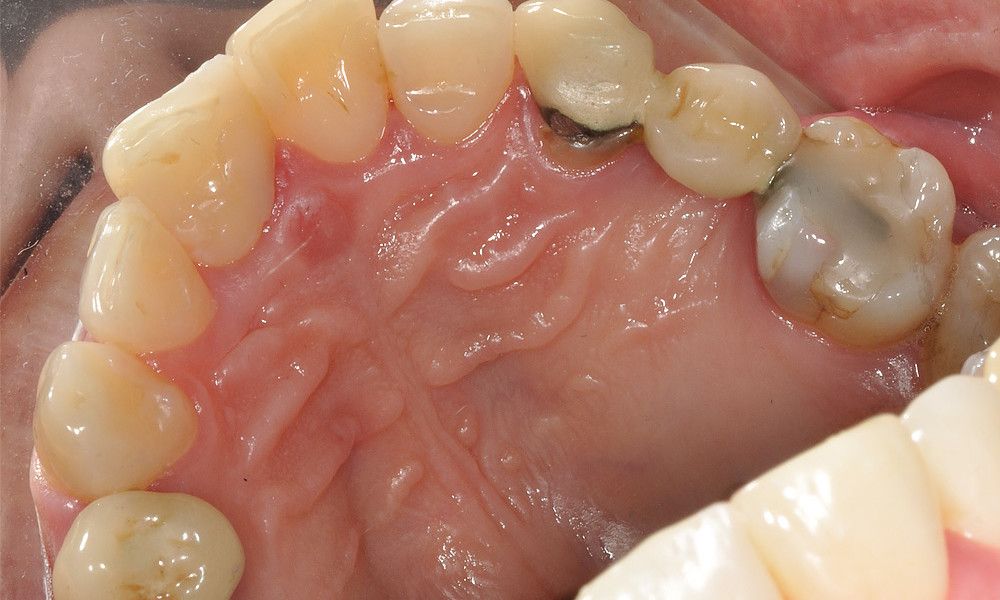

Reporte del Caso: Paciente sexo masculino, 36 años, con diagnóstico de esquizofrenia y trastorno bipolar en tratamiento. Consulta por el recambio de dos prótesis fijas plurales (PFP) de reemplazo de dientes 4 y 13 con pilares en piezas 3, 5, 12 y 14 mediante rehabilitaciones unitarias de los dientes pilares y reemplazo mediante implantes en zonas edéntulas.

El estudio imagenológico evidencia una pérdida ósea severa en altitud y grosor, situación que complejiza la colocación de un implante. Se analizan alternativas de tratamiento y se opta por una vestibuloplastía mediante autoinjerto conectivo de mucosa palatina que se reposiciona sobre la zona del defecto óseo. Además se realiza retratamiento de ambas PFP, ahora en zirconia, por motivos estéticos y oclusales. Se realizan controles posteriores para evaluar la respuesta gingival a la vestibuloplastía.